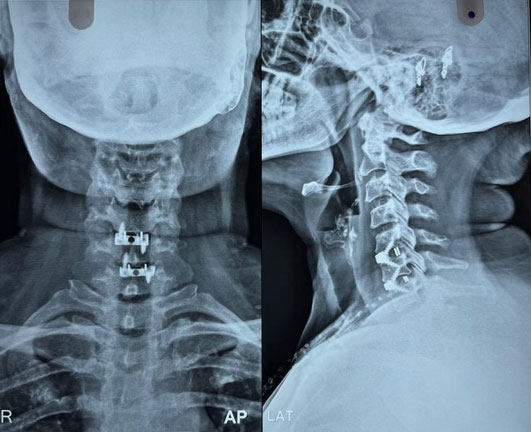

Surgical Highlights